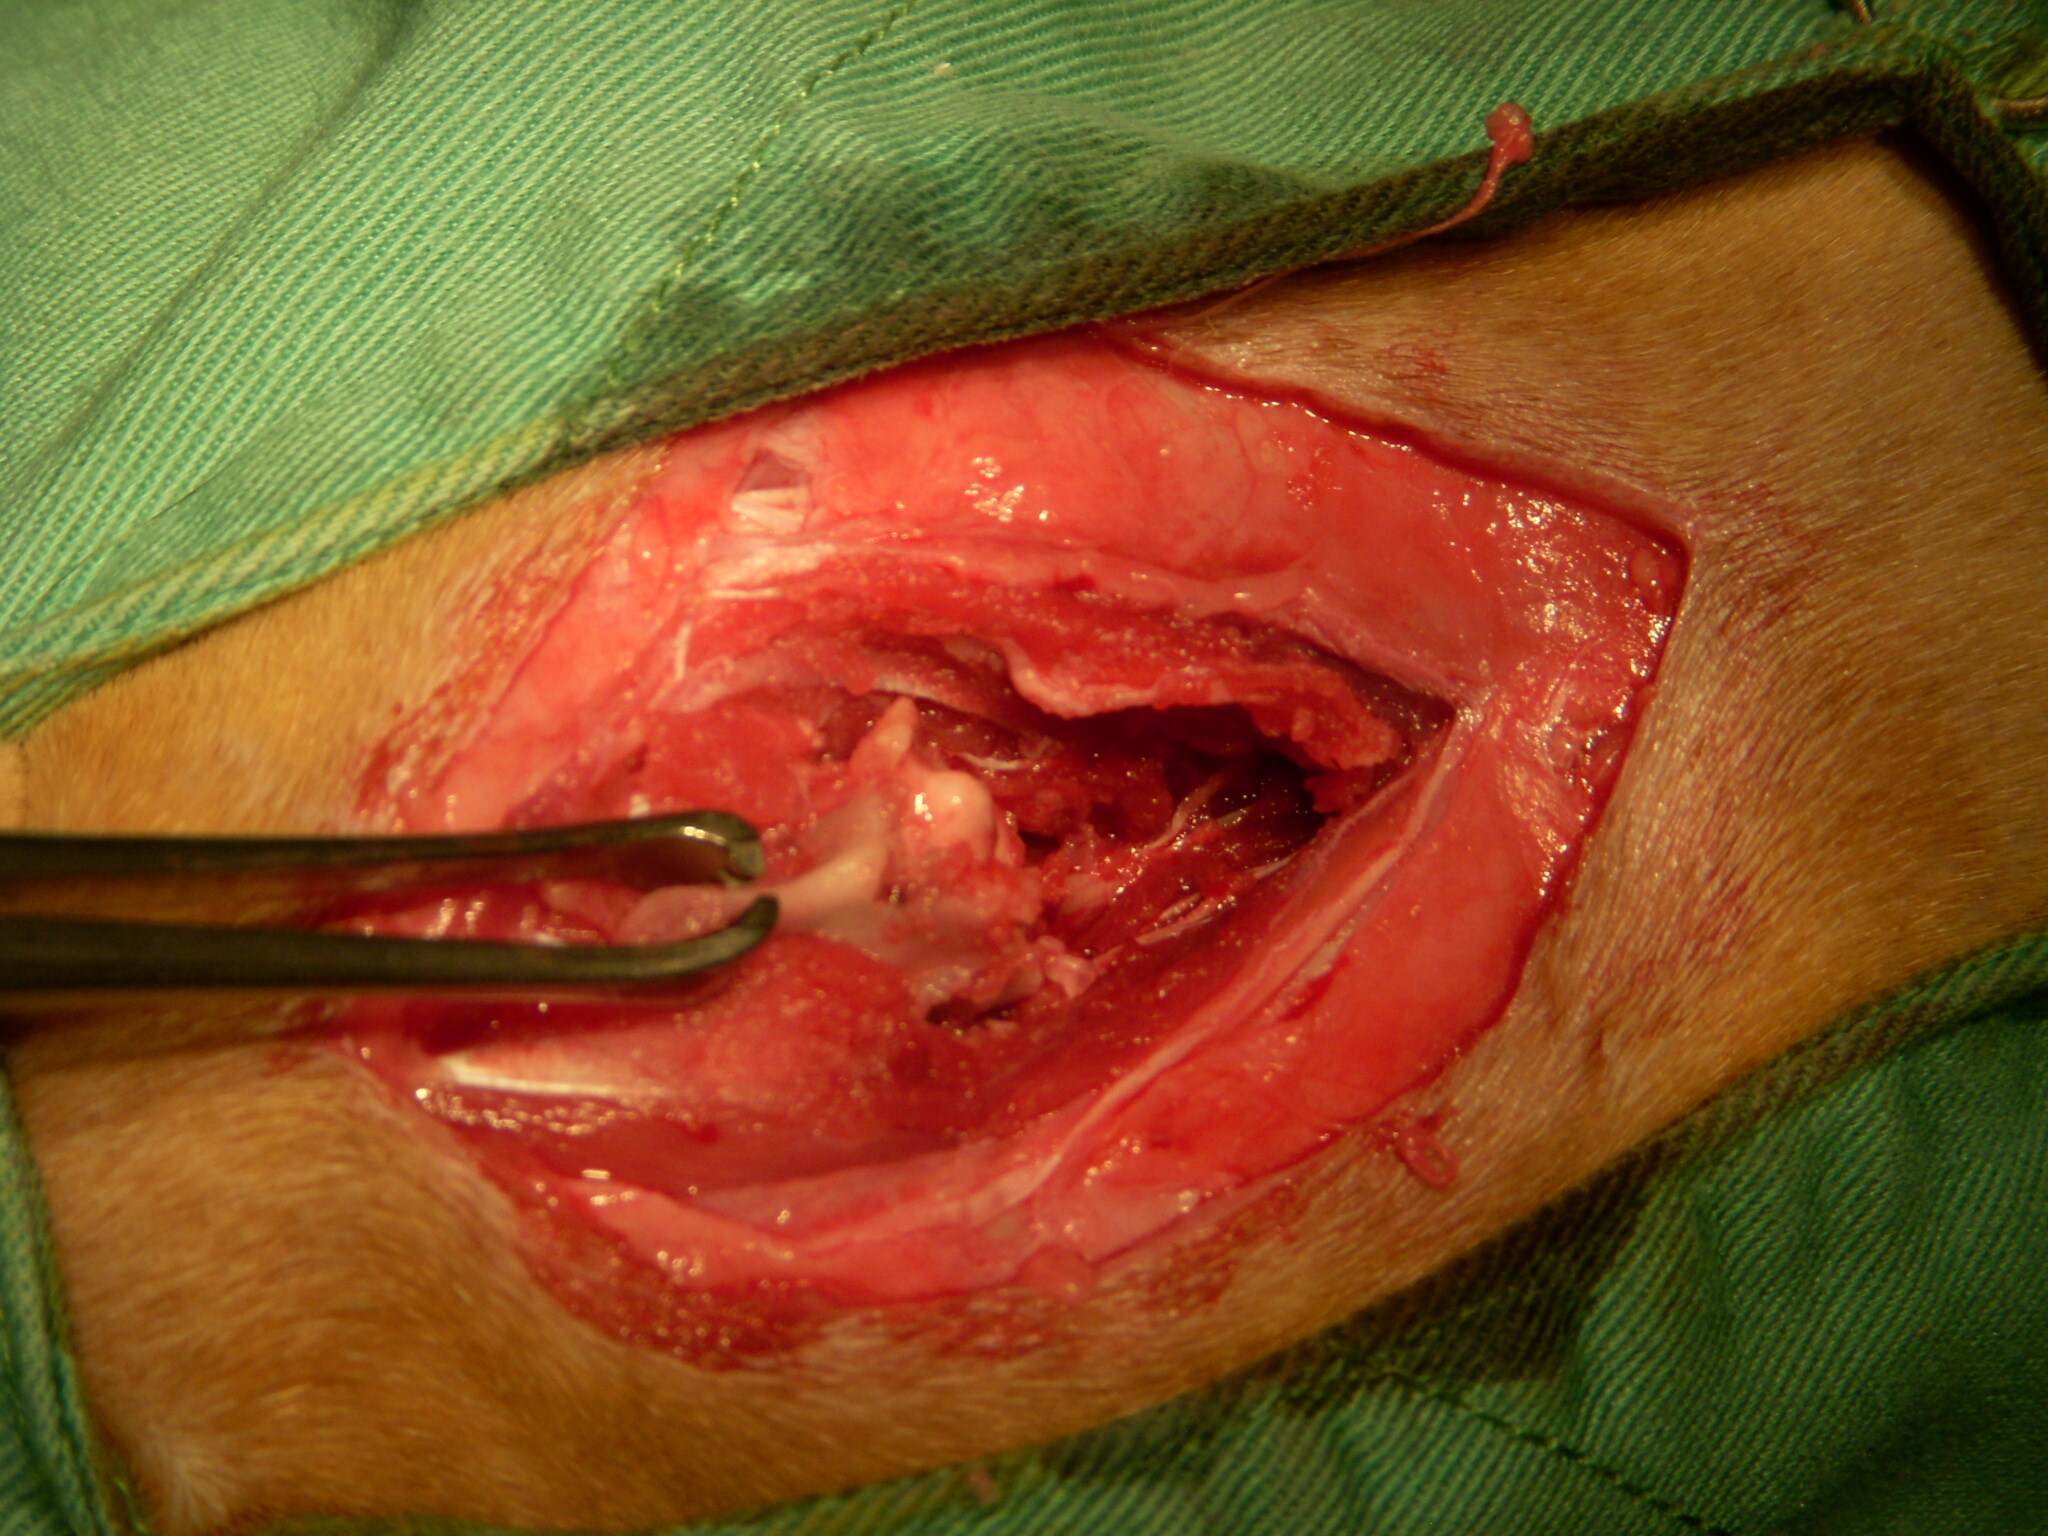

主題: 三清宮狗咬斷腰椎貓 申請者姓名: 岳丹楓 花色: 申請日期: 2012-11-07 15:17:35 申請者部落格: 申請者臉書網址: 所在縣市/合作醫院: 台北市/恩加動物醫院 治療費用: 18900元 需求人數: 20人 已結案 (2013-06-27 13:53:51) 報名人員: 婷(已付款)、桑尼(已付款)、Jennifer Su(已付款)、Kelly Chen(已付款)、Cecilia Shih(已付款)、Jimmy Li Li(已付款)、吉兒(已付款)、Min-Hua LI(已付款)、吳亭亭(已付款)、陳玲心(已付款)、Flora Chen(已付款)、curry0、yi(已付款)、timel0607(已付款)、海倫(已付款)、curry0(已付款)、curry0(已付款)、Elly(已付款)、Yu Chiu(已付款)、桂芳手藝行(小咪)(已付款)、周菁(已付款)、 候補人員: 肥美貓、 動物病情說明: 這是一隻在三清宮餵養的時候看到的受傷貓,因為這裡也有很多流浪狗,可能是附近的野狗咬傷的,受傷地方剛好是腰部有四個明顯的傷口,X光下可以看到腰椎整個斷裂,經過生命跡象穩定之後,雖然下半身已經癱瘓,但是看他那麼灑嬌的模樣,決定幫他做脊椎固定手術,以方便將來生存活動,現在他傷口都復原了,只是需要包尿布,他真的很撒嬌,叫人真的很捨不得,希望大家多多幫忙。